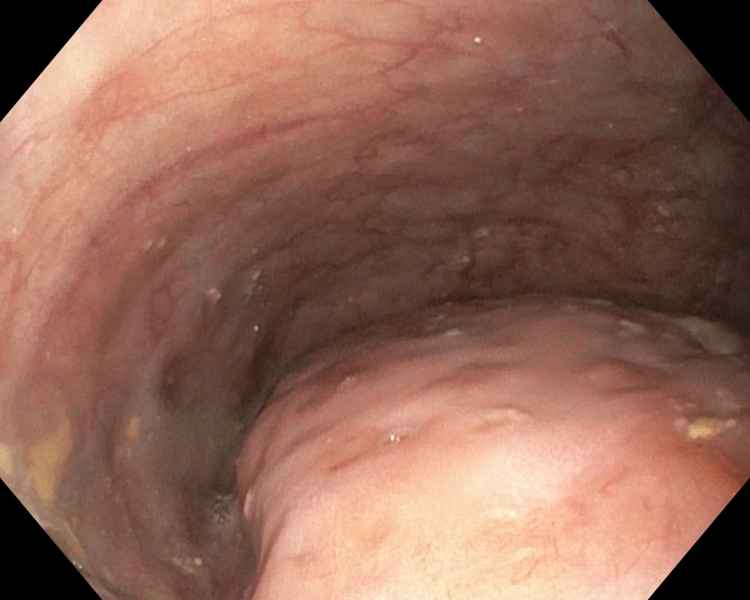

An uncommon cause of dysphagia

Fotografia